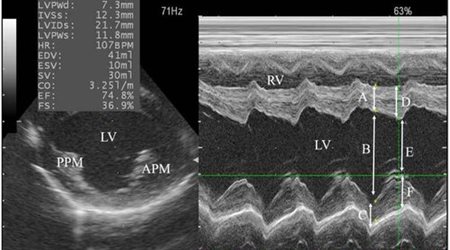

اکوکاردیوگرافی 🔗

Echocardiography